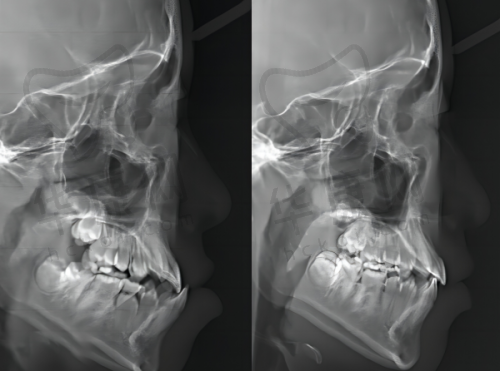

大连奥美口腔在硬件设施方面投入巨大。医院配备了精良的口腔CT设备,能够清晰正确地获取患者口腔内部的三维结构信息,为瑞士士卓曼ITI种植牙手术提供严谨的术前诊断和方案设计依据。同时,拥有无菌的种植手术室,严格遵循消毒流程,大大降低了手术感染的风险,保护了种植牙手术的安心性和成功几率。

大连奥美口腔的医生团队在瑞士士卓曼ITI种植牙领域经验多。他们大多毕业于有名口腔医学校校,经过多年的临床实践和专精培训,熟练掌握了瑞士士卓曼ITI种植牙的精良技术。例如,医生们能够根据患者的口腔实际情况,如牙槽骨的密度、高度、宽度等,精细地选择合适的种植体型号和植入位置,确保种植牙与患者口腔环境理想适配。

在手术操作方面,医生们手法娴熟、技艺不错。他们能够在尽量减少对患者口腔组织损伤的前提下,快速、正确地完成瑞士士卓曼ITI种植牙植入手术,缩短手术时间,减轻患者的痛苦。同时,医生们还会不断关注口腔种植领域的全新研究成果和技术发展趋势,积极参加国内外的学术交流活动,将全新的理念和技术应用到临床实践中,为患者提供更优质的治疗方案。